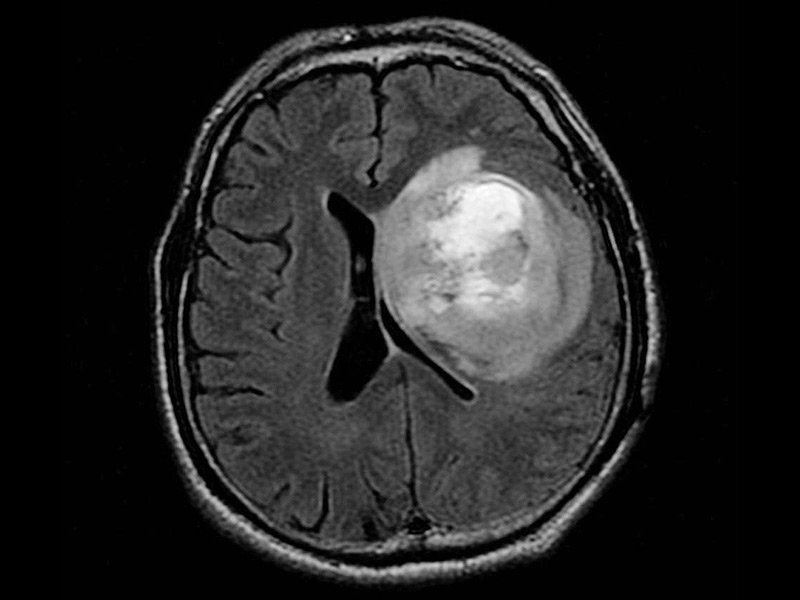

神经胶质瘤是在中枢神经系统的神经胶质细胞中形成的脑癌或脑肿瘤。胶质细胞是围绕并支持神经细胞的那些。一些脑癌起源于身体其他部位,而神经胶质瘤则起源于中枢神经系统,通常被称为“原发性”脑瘤。脑胶质瘤的治疗方法有哪些?相关阅读:8岁女孩5cm较大基底节区脑瘤成功切除记,除了其起源的位置以外,神经胶质瘤还具有许多特征。恶性神经胶质瘤的一个重要特征是它们没有清晰可辨的界限或“弥漫性”。即使被去除,部分神经胶质瘤也经常残留并导致复发。虽然神经胶质瘤不会扩散到中枢神经系统之外,但在疾病的复发阶段,通常会在整个脑干中发现多个神经胶质瘤。

脑胶质瘤的外科手术,主要以减少肿瘤细胞数量,减少肿瘤负荷,减轻颅腔压力,减除神经功能缺失为目的。目前的胶质瘤手术,已经进入了一个微创时代,与前相比,更为顺利,创伤更为小,肿瘤切除更为完全。显微镜应用于脑胶质瘤的切除,可以更加清晰地辨别肿瘤与脑组织的边界,以及周围重要的神经血管等结构,从而能够在顺利的情况下,较大化地切除胶质瘤。神经导航的应用,将胶质瘤的手术切除,提高到新的高度。神经导航与汽车导航相类似,可以使外科医生在手术前从切口的设计、术中功能脑区的辨认以及手术切除方式的选择等方面,更加精确和细化。